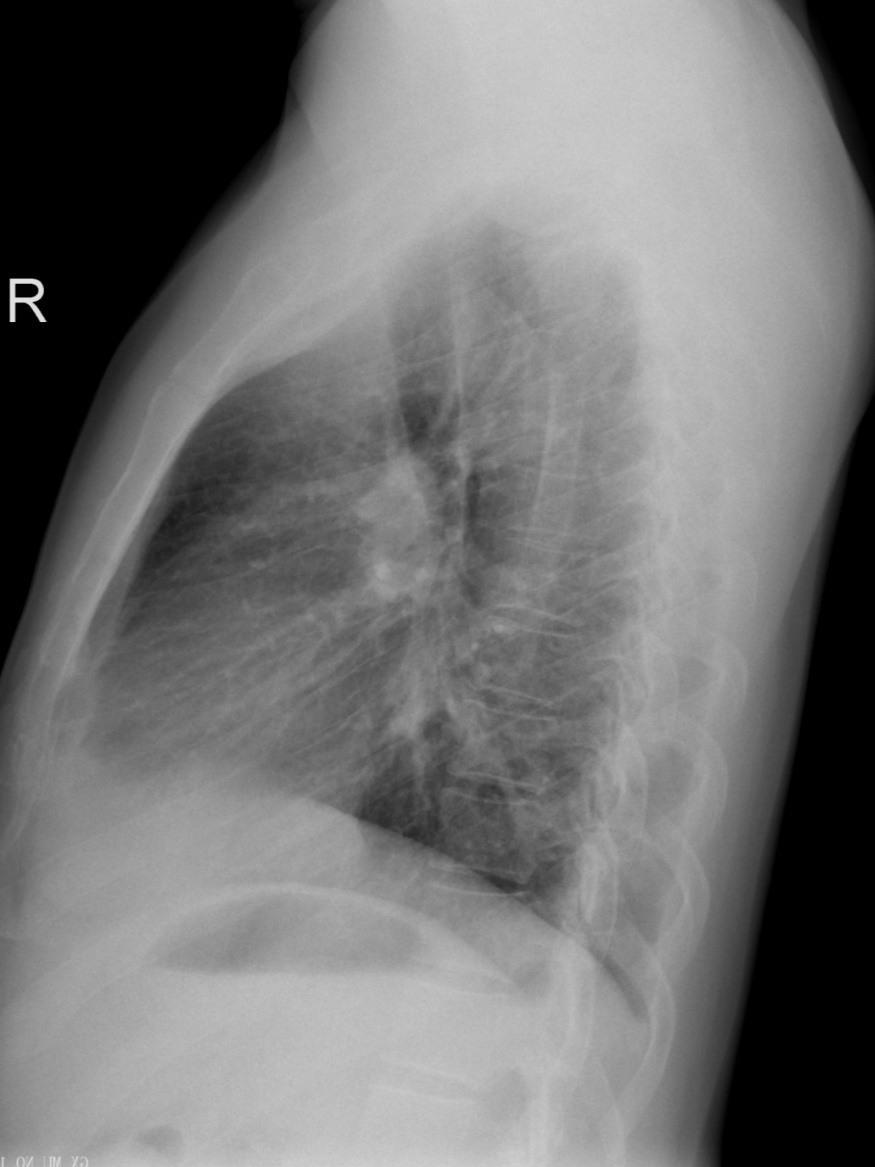

(胸部ct图像)

CT全称是Computed Tomography(计算机断层成像),与普通X线一样,都是以X线穿透人体为基础,不过是分层连续扫描,形成断层图像,没有重叠,能看清楚器官之间的空间位置关系,也可以通过计算机进行后处理,得到曲面重组、最大密度投影法、容积再现技术、CTA等不同应用的图像。缺点是:辐射剂量相对大,价格贵。

曲面重组图像

最大密度投影